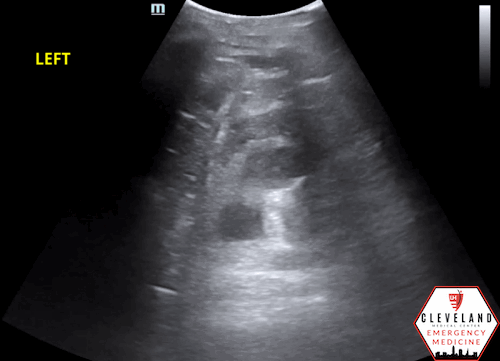

POCUS findings:

Dilated renal pelvis with multiple coalescing, anechoic calyces and parenchymal thinning, consistent with severe hydronephrosis bilaterally — new on the left, with more cortical thinning noted on the right. The bladder (not shown here) was fully decompressed.

**Both of this patient’s kidneys appear to have grade 4 or severe hydronephrosis based on ultrasound.